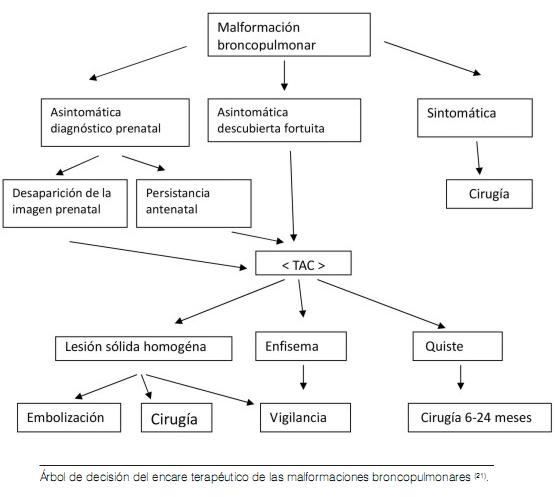

La terapéutica depende de la evolución espontánea de las lesiones, y del carácter sintomático o no. Así, se indica vigilancia estricta clínica y radiológica cuando se trata de un ELC asintomático, sin riesgo vital (respiratorio y/o cardiovascular) (1,11,21) o sobre todo si la exploración broncoscópica es normal (28). En la literatura se describe un caso de seguimiento de un niño con ELC hasta la edad de 17 años (25).

Sin embargo, cuando se trata de un ELC sintomático, una lobectomía por toracotomía y/o toracoscopía con cuidado en reanimación son necesarios (1, 11, 21,28). La evolución es a menudo favorable con expansión pulmonar hasta de 90%. A veces se puede ver hipertensión arterial pulmonar secundaria (25-27).

El ELC es una malformación pulmonar rara que puede poner en peligro el pronóstico vital del recién nacido afectado. El diagnóstico es sobre todo radiológico. La TAC torácica informa con precisión las características y topografía de las lesiones. La biopsia confirma el diagnóstico. La lobectomía está indicada cuando el niño es sintomático. En el caso de un paciente asintomático, el manejo conservador es el tratamiento de elección.